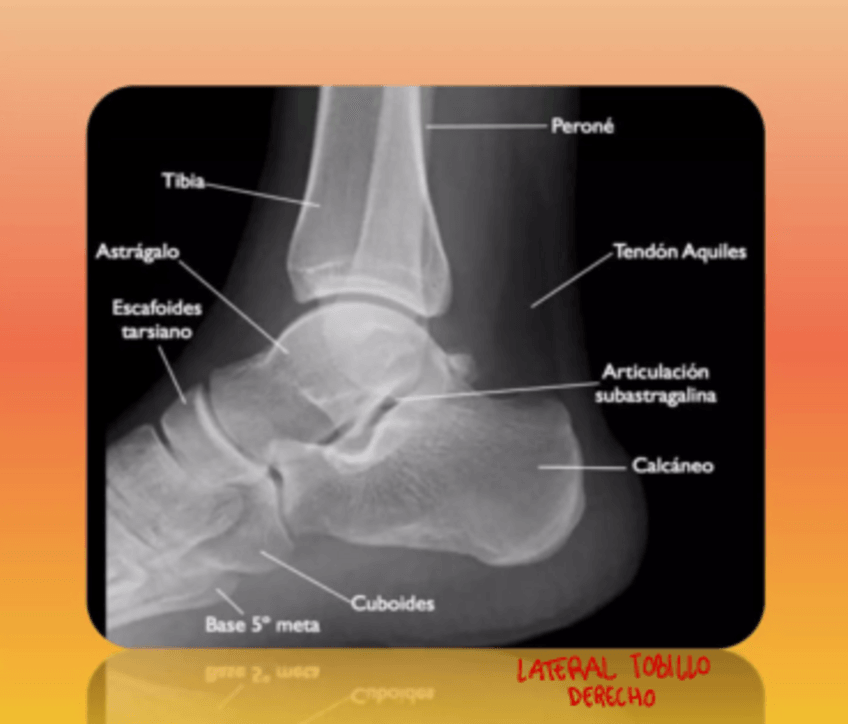

Pie, tobillo, rodilla y cadera